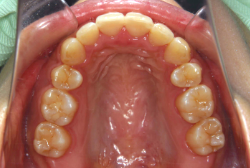

「隙間を閉じたい」という主訴で来院したケースです。診断の結果、「空隙歯列弓+軽度叢生」と判明しましたが、この方の場合は上は隙がある、つまりスペースが余っているのに対して、下は軽度の凸凹がある、つまりスペースが足りないと言う状態でした。

通常、凸凹の症状の場合は、小臼歯を抜歯させていただくのですが、この方の場合は凸凹も軽度で親知らずもないため、非抜歯で対応することになりました。マルチブラケット装置にて治療を開始し、治療期間は11ヶ月でした。治療後は正中の空隙が閉鎖されただけでなく、下の凸凹と下の歯並びの形態そのものが大幅に改善されました。もちろん噛み合わせ的にも正しい状態が確立しています。